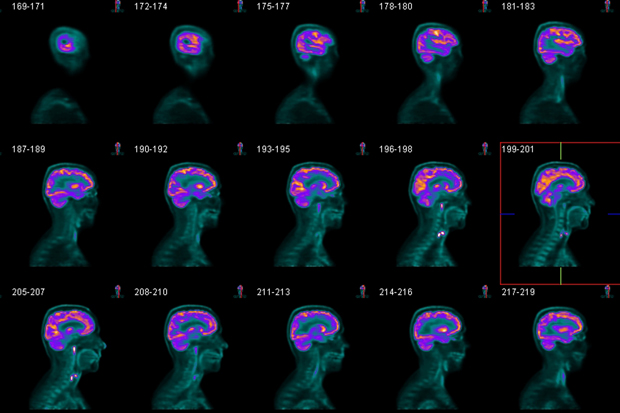

In the cult Steve Martin film The Man With Two Brains, a doctor falls in love with a surgically removed brain. The object of his desire (fizzing, if I remember rightly, in a demijohn of formaldehyde) makes for an enduring gothic comedy of the mind. On the movie’s release in the early 1980s, neuroscience was still in its infancy. Men in white coats were cutting up monkey brains and their laboratories smelled of monkey urine. In recent years, however, neuro-imaging has changed the study of the human mind completely. Rainbow-coloured images on the scanner screen reveal our most precious and mysterious organ in all its alien complexity.